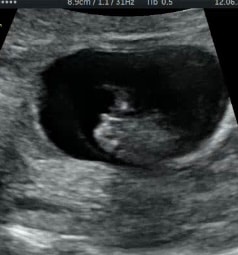

Алина

Мне кажется девочка. У мальчика как бы шарик на кончике, а у девочки вилочка, или бугорок вообще сужается к кончику. Вот это мальчик 11.1 срок.

Но конечно в 12 недель очень легко перепутать, вот в 13 полных уже лучше видно именно по бугорку, там девочку видно хорошо

На сколько тут смотрела , с таким наклоном встречаются и мальчики и девочки..

Но по-вашему снимку всё-таки девчушка думаю

Кажется у нас похожие ракурсы узи на этом сроке, прикладываю свой для сравнения посмотреть, на втором скрининге узнали, что у нас мальчишка! Хотя тут были все комментарии, что 100 % девочка. Так что ждите гарантированный второй скрининг 😁